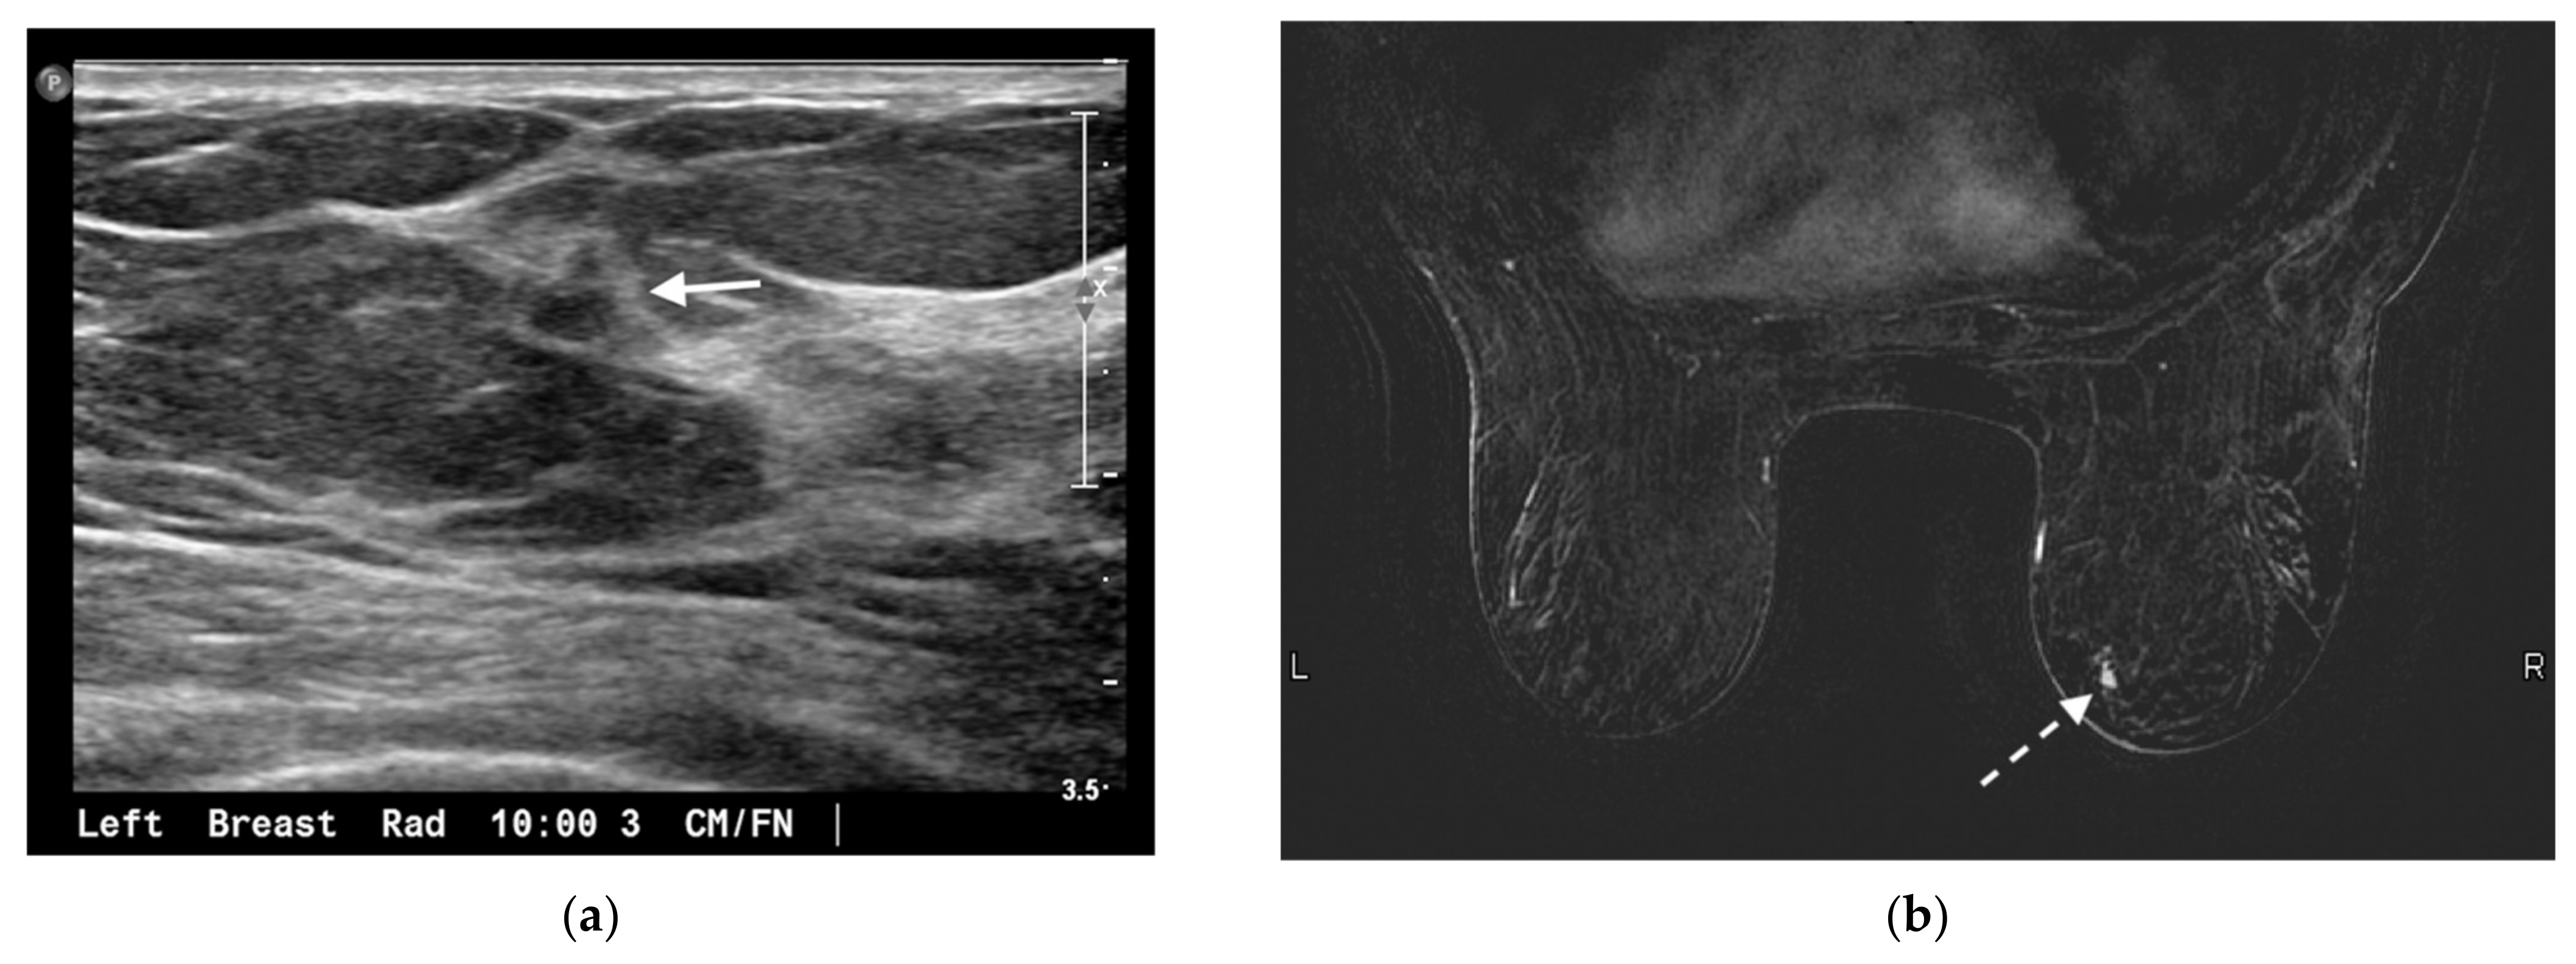

- Croshaw, R.; Shapiro-Wright, H.; Svensson, E.; Erb, K.; Julian, T. Accuracy of clinical examination, digital mammogram, ultrasound, and MRI in determining postneoadjuvant pathologic tumor response in operable breast cancer patients. Ann. Surg. Oncol. 2011, 18, 3160–3163. [Google Scholar] [CrossRef] [PubMed]

- Sheikhbahaei, S.; Trahan, T.J.; Xiao, J.; Taghipour, M.; Mena, E.; Connolly, R.M.; Subramaniam, R.M. FDG-PET/CT and MRI for Evaluation of Pathologic Response to Neoadjuvant Chemotherapy in Patients With Breast Cancer: A Meta-Analysis of Diagnostic Accuracy Studies. Oncologist 2016, 21, 931–939. [Google Scholar] [CrossRef] [PubMed] [Green Version]

- Mukhtar, R.A.; Yau, C.; Rosen, M.; Tandon, V.J.; Hylton, N.; Esserman, L.J. Clinically meaningful tumor reduction rates vary by prechemotherapy MRI phenotype and tumor subtype in the I-SPY 1 TRIAL (CALGB 150007/150012; ACRIN 6657). Ann. Surg. Oncol. 2013, 20, 3823–3830. [Google Scholar] [CrossRef] [Green Version]

- Denis, F.; Desbiez-Bourcier, A.; Chapiron, C.; Arbion, F.; Body, G.; Brunereau, L. Contrast enhanced magnetic resonance imaging underestimates residual disease following neoadjuvant docetaxel based chemotherapy for breast cancer. Eur. J. Surg. Oncol. 2004, 30, 1069–1076. [Google Scholar] [CrossRef]

- Schrading, S.; Kuhl, C.K. Breast Cancer: Influence of Taxanes on Response Assessment with Dynamic Contrast-enhanced MR Imaging. Radiology 2015, 277, 687–696. [Google Scholar] [CrossRef]

- Chen, J.-H.; Bahri, S.; Mehta, R.S.; Carpenter, P.M.; McLaren, C.E.; Chen, W.-P.; Fwu, P.T.; Hsiang, D.J.B.; Lane, K.T.; Butler, J.A.; et al. Impact of factors affecting the residual tumor size diagnosed by MRI following neoadjuvant chemotherapy in comparison to pathology. J. Surg. Oncol. 2014, 109, 158–167. [Google Scholar] [CrossRef] [PubMed] [Green Version]

- Reig, B.; Lewin, A.A.; Du, L.; Heacock, L.; Toth, H.K.; Heller, S.L.; Gao, Y.; Moy, L. Breast MRI for Evaluation of Response to Neoadjuvant Therapy. Radiographics 2021, 41, 665–679. [Google Scholar] [CrossRef] [PubMed]